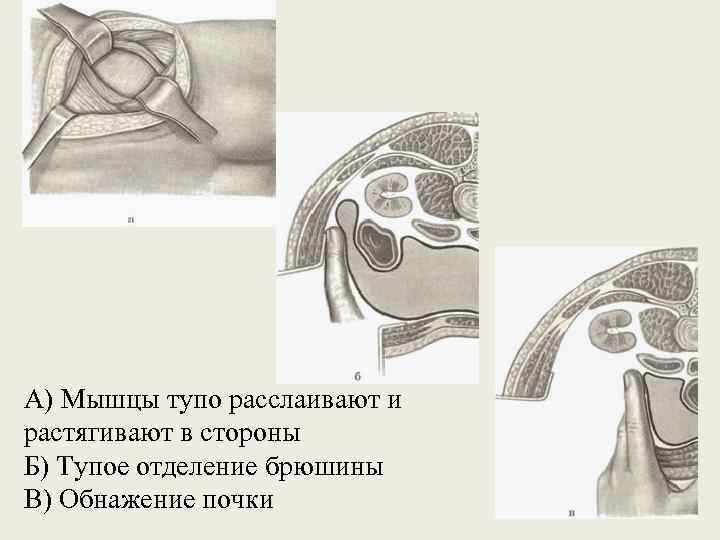

А) Мышцы тупо расслаивают и растягивают в стороны Б) Тупое отделение брюшины В) Обнажение почки

Люмботомия по Федорову • Наиболее употребительна в настоящее время • Больного укладывают на здоровый бок на валике • Ногу на больной стороне выпрямляют, на здоровой сгибают в тазобедренном и коленном • Разрез начинают от угла, образованного XII ребром и длинными мышцами спины, проводят под XII ребром в косопоперечном направлении к пупку • При высоком расположении почки используют межреберный доступ (XI и XII) • Рассекают кожу, подкожную жировую клетчатку, поверхностную фасцию, послойно рассекают мышцы. Брюшину тупым путем отделяют от почечной фасции и оттягивают вниз и кпереди • Задний листок собственной фасции почки вскрывают и, тупо раздвигая околопочечную жировую клетчатку, обнажают почку